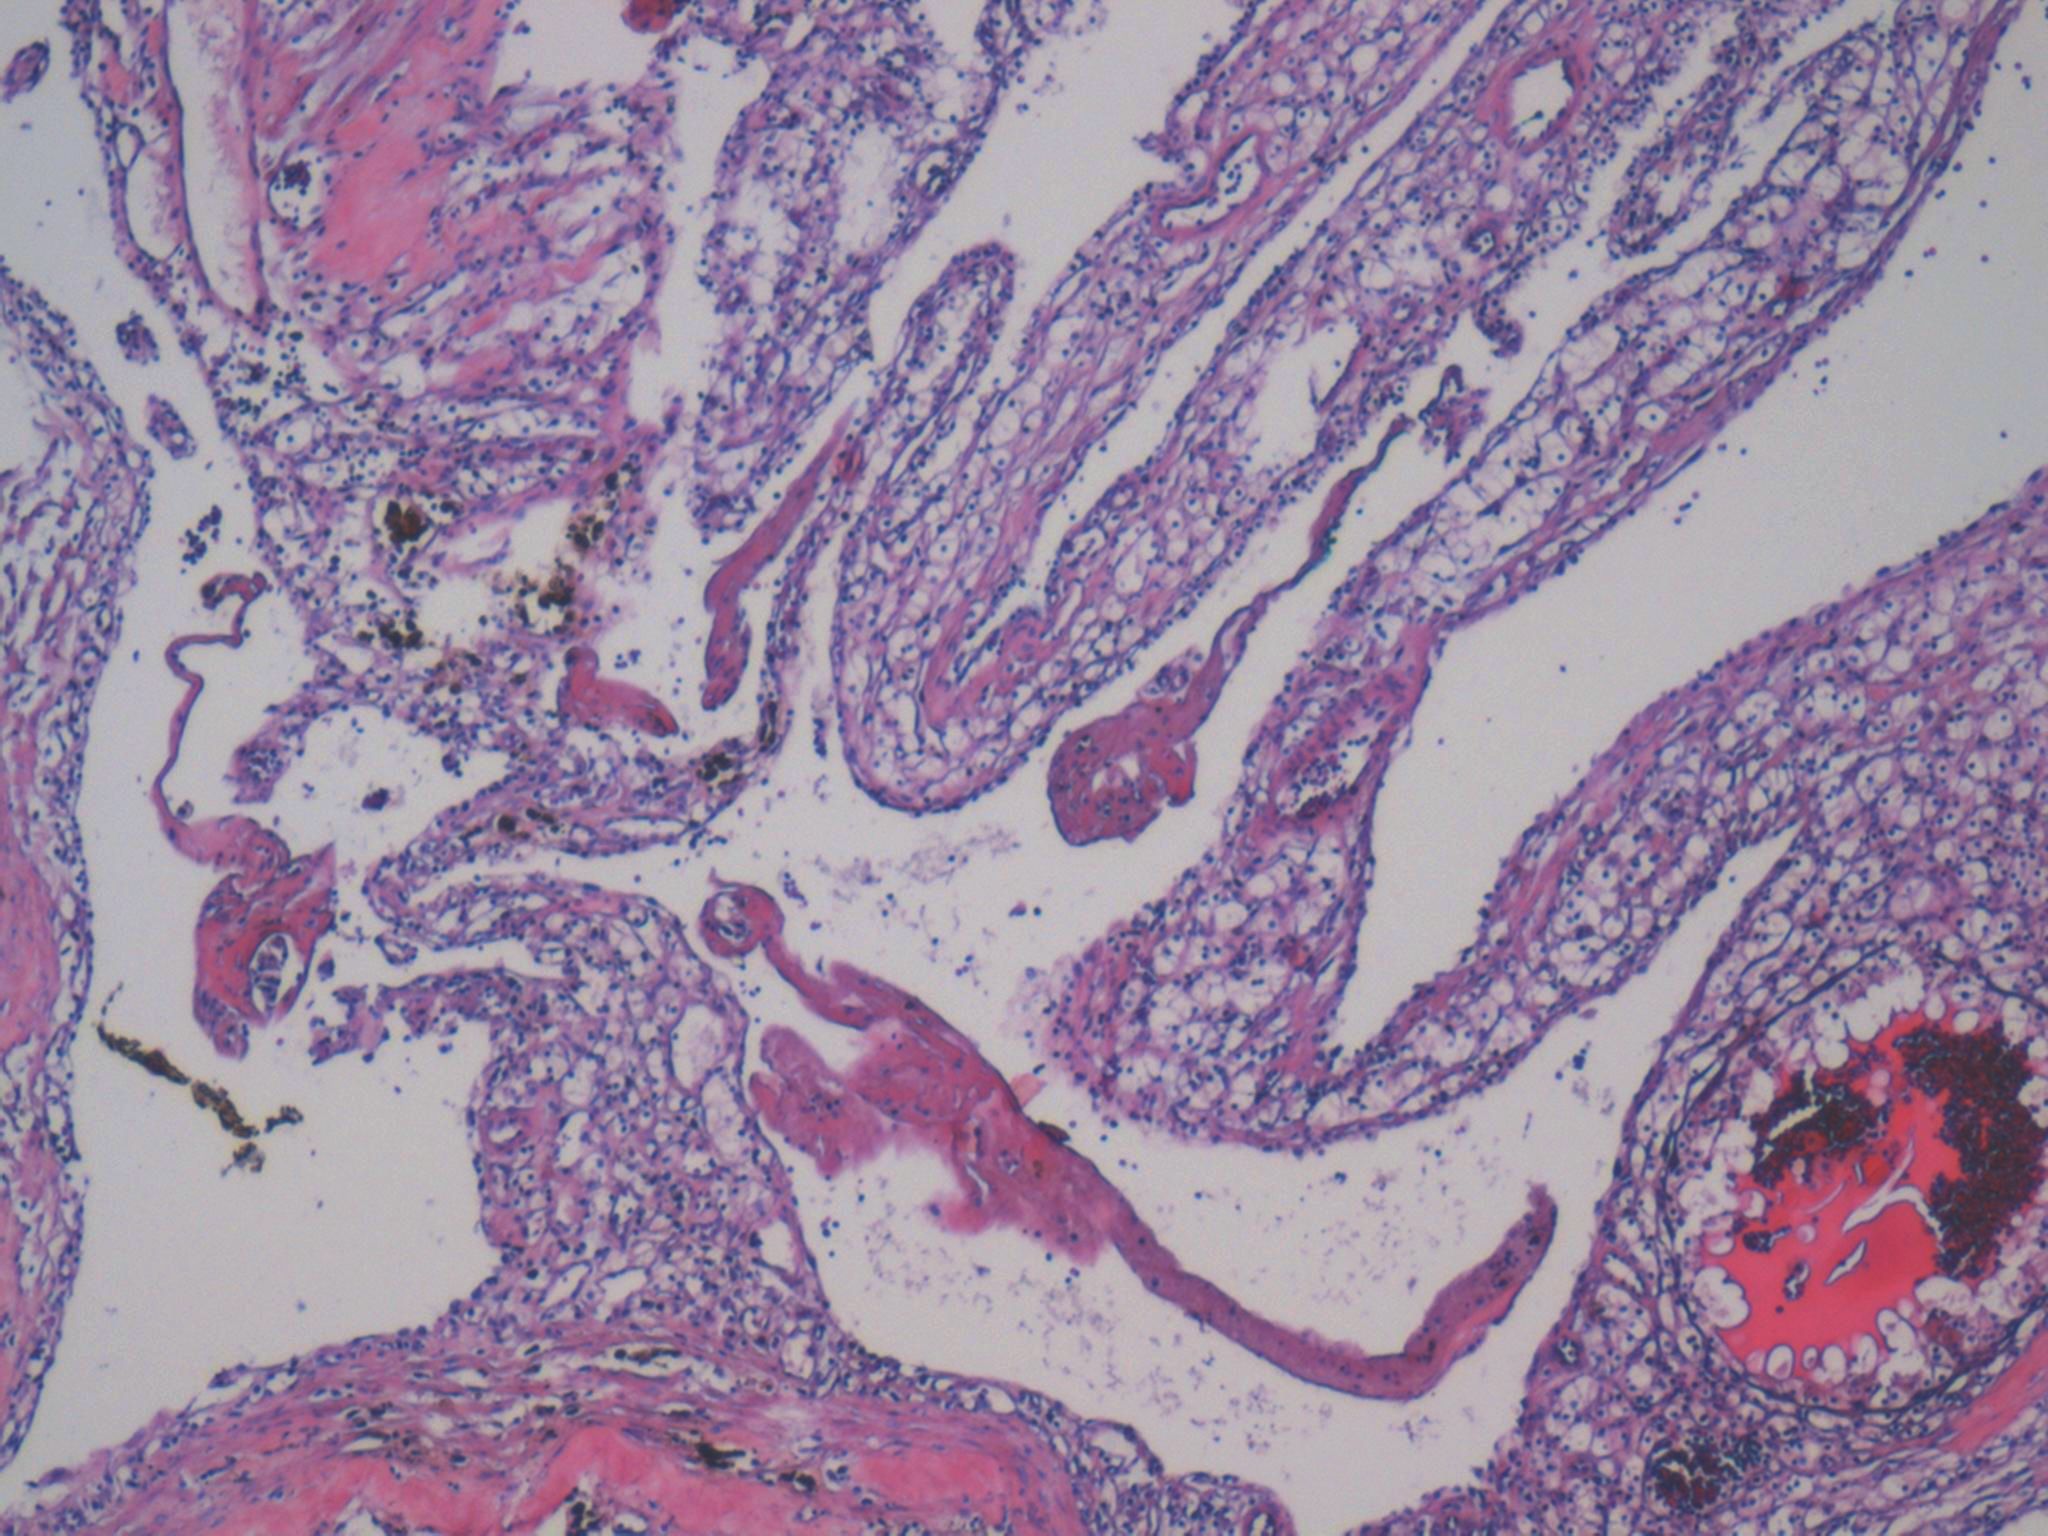

Consensus grade: Clear cell RCC

clear cell RCC with cystic changes

I would like to see overall appearance, my second dg would be multilocular multicystic renal cell neoplasm of low malignant potential. But septa of given tumor are too broad, too tick for my (my opinion).

Cystic tumour with clear cells.